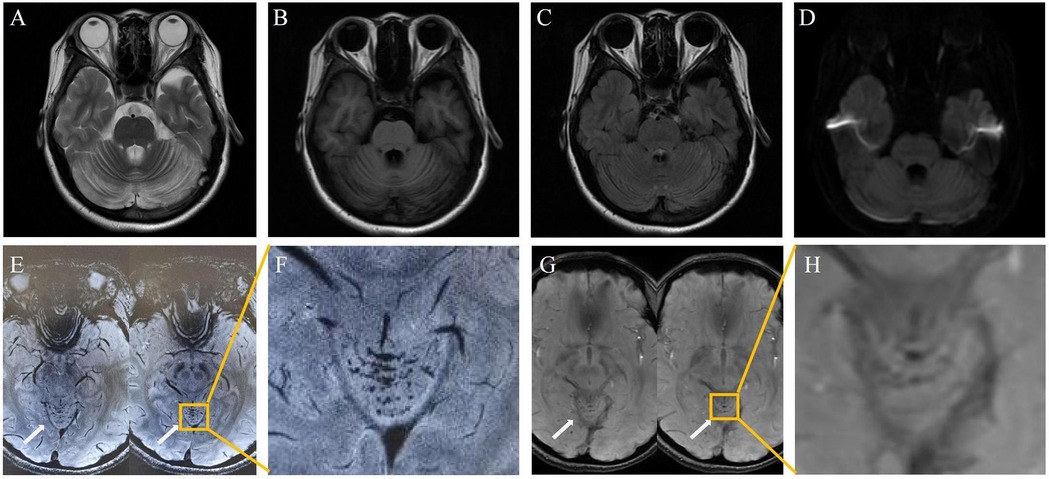

Investigations revealed severe anemia (hemoglobin 93 g/L, ref: 114–154 g/L) and hyperhomocysteinemia (210 µmol/L, ref: ≤15 µmol/L). Laboratory investigations also revealed an elevated blood propionylcarnitine/acetylcarnitine ratio (C3/C2: 0.21; ref: 0.02–0.20) and significantly increased urinary methylmalonic acid (17.5; ref: 0.0–4.0) with mild methylcitric acid elevation (0.8; ref: 0.0–0.7) on tandem mass spectrometry and organic acid analyses. Cranial MRI showed bilateral cerebellar hyperintensities on MRI DWI/FLAIR (Figure 1). Whole-exome sequencing identified compound heterozygous MMACHC mutations (c.80A > G, c.482G > A), confirming a diagnosis of cblC-type MMA-HC.

The symptoms resolved gradually following a one-month course of treatment, which included intramuscular injection of mecobalamin (500 μg once daily), as well as oral administration of vitamin B6 (10 mg three times daily), folic acid (5 mg once daily), and idebenone (30 mg three times daily). Follow-up 3.0 T MRI showed significant resolution of the cerebellar lesions on DWI and FLAIR (Figure 2A–D). Crucially, 7.0 T and 3.0 T MRI SWI revealed multiple punctate microhemorrhages in the cerebellar vermis (Figure 2E–H). The long-term treatment plan for the patient consists of lifelong medication including intramuscular injection of mecobalamin 500 μg once daily—to be reduced to once weekly after homocysteine levels stabilize—along with oral folic acid 5 mg once daily, and oral vitamin B6 10 mg three times per day. In addition, regular monitoring of plasma homocysteine, folate levels, and renal function is recommended, with dosage adjustments made based on the results.

Figure 2. Post-treatment: cerebellar lesion resolution [(A–D), 3.0 T]; vermian microhemorrhages on 7.0 T SWI (E,F) and 3.0 T SWI (G,H).